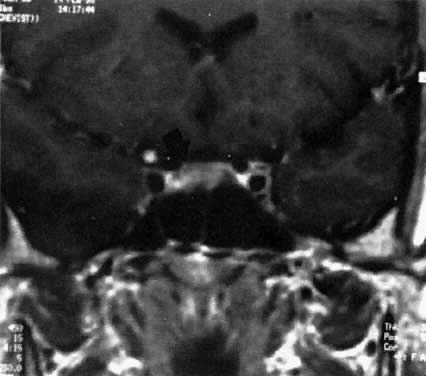

Fig. 1. Magnetic resonance imaging scan of patient with a prolactin-secreting microadenoma ( arrow ).